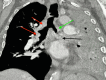

Tracheobronchial amyloidosis is a rare condition characterized by the deposition of amyloid proteins in the trachea and bronchi, leading to significant respiratory symptoms such as chronic mucoid, cough, dyspnea, and recurrent respiratory infections. We present the case of a 61-year-old individual who developed tracheobronchial amyloidosis, which poses a diagnostic challenge due to its clinical and radiological resemblance to other pulmonary disorders, including chronic bronchitis. Histologically, tracheobronchial amyloidosis is characterized by the presence of amyloid deposits confirmed by Congo red staining, which shows apple-green birefringence under polarized light. Further confirmation can be obtained through electron microscopy, revealing non-branching fibrils. This report explores the clinical presentation, diagnostic challenges, and management of tracheobronchial amyloidosis. Therapeutic interventions may include bronchoscopic procedures to remove obstructive amyloid deposits and systemic treatments such as chemotherapy or immunotherapy to address the underlying amyloid process, aiming to improve patient outcomes and quality of life.